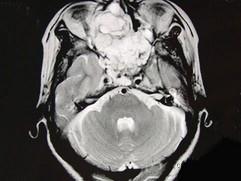

问题 女性,41岁,鼻腔流脓涕3年,鼻部面部肿胀1年,近来加重,MRI检查如图,请选择最可能诊断 ( )

选项 A、鼻咽癌 B、鼻腔血管瘤 C、鼻腔内出血 D、鼻腔软骨瘤 E、鼻腔内囊肿

答案 D